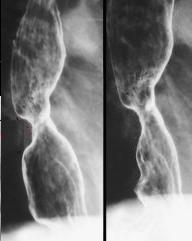

Image

radiologique de tuberculose de oesophage en TOGD :

Bord de oesophage est crenele par des petites

ulceres . Deux diverticule a type traction au tier

superieure de oesophage . |

Image TOGD

du diverticule de type traction de oesophage

associe de images creneles de ulcere multiple au

bord de oesophage . |

Image de oesophagite en TOGD ++

double de contrast . Image en crenele en ce cas se

voyaient tres net . Image de diverticule de type

traction avec retention de baryte en niveau . |